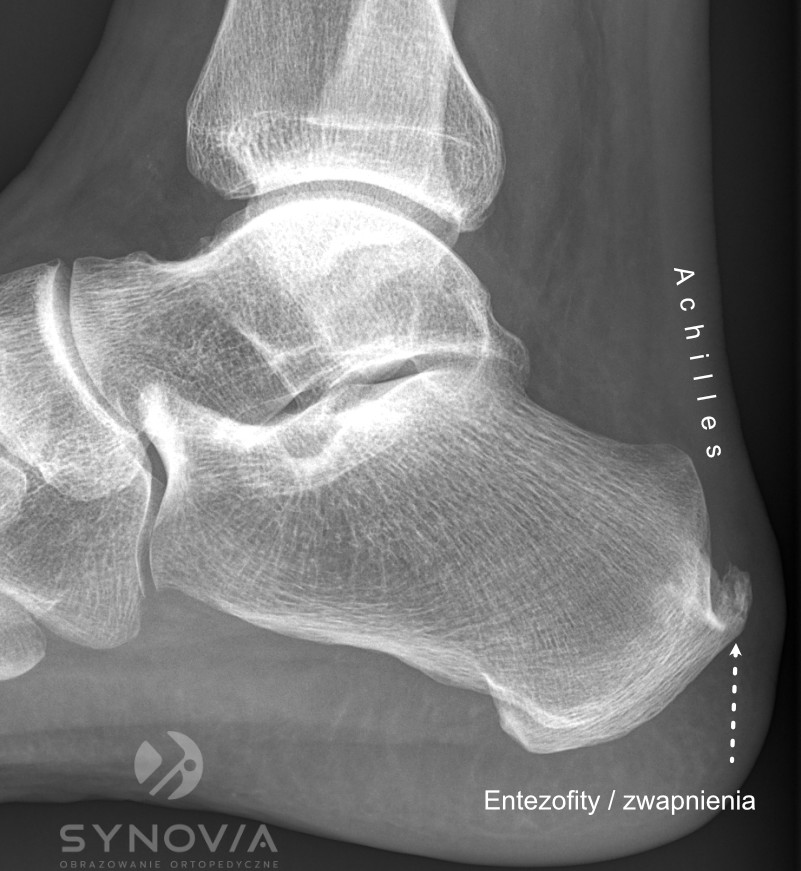

RTG

Co widać: Entezofity – kostne wyrostki w miejscu przyczepu, ewentualnie nadżerki kości (w chorobach reumatycznych).

Badanie RTG stopy Wykonywane w celu oceny struktury kostnej i wykluczenia zmian w obrębie kości piętowej. Szczególnie przydatne w diagnostyce ostrogi piętowej, entezofitów oraz zmian zwyrodnieniowych.